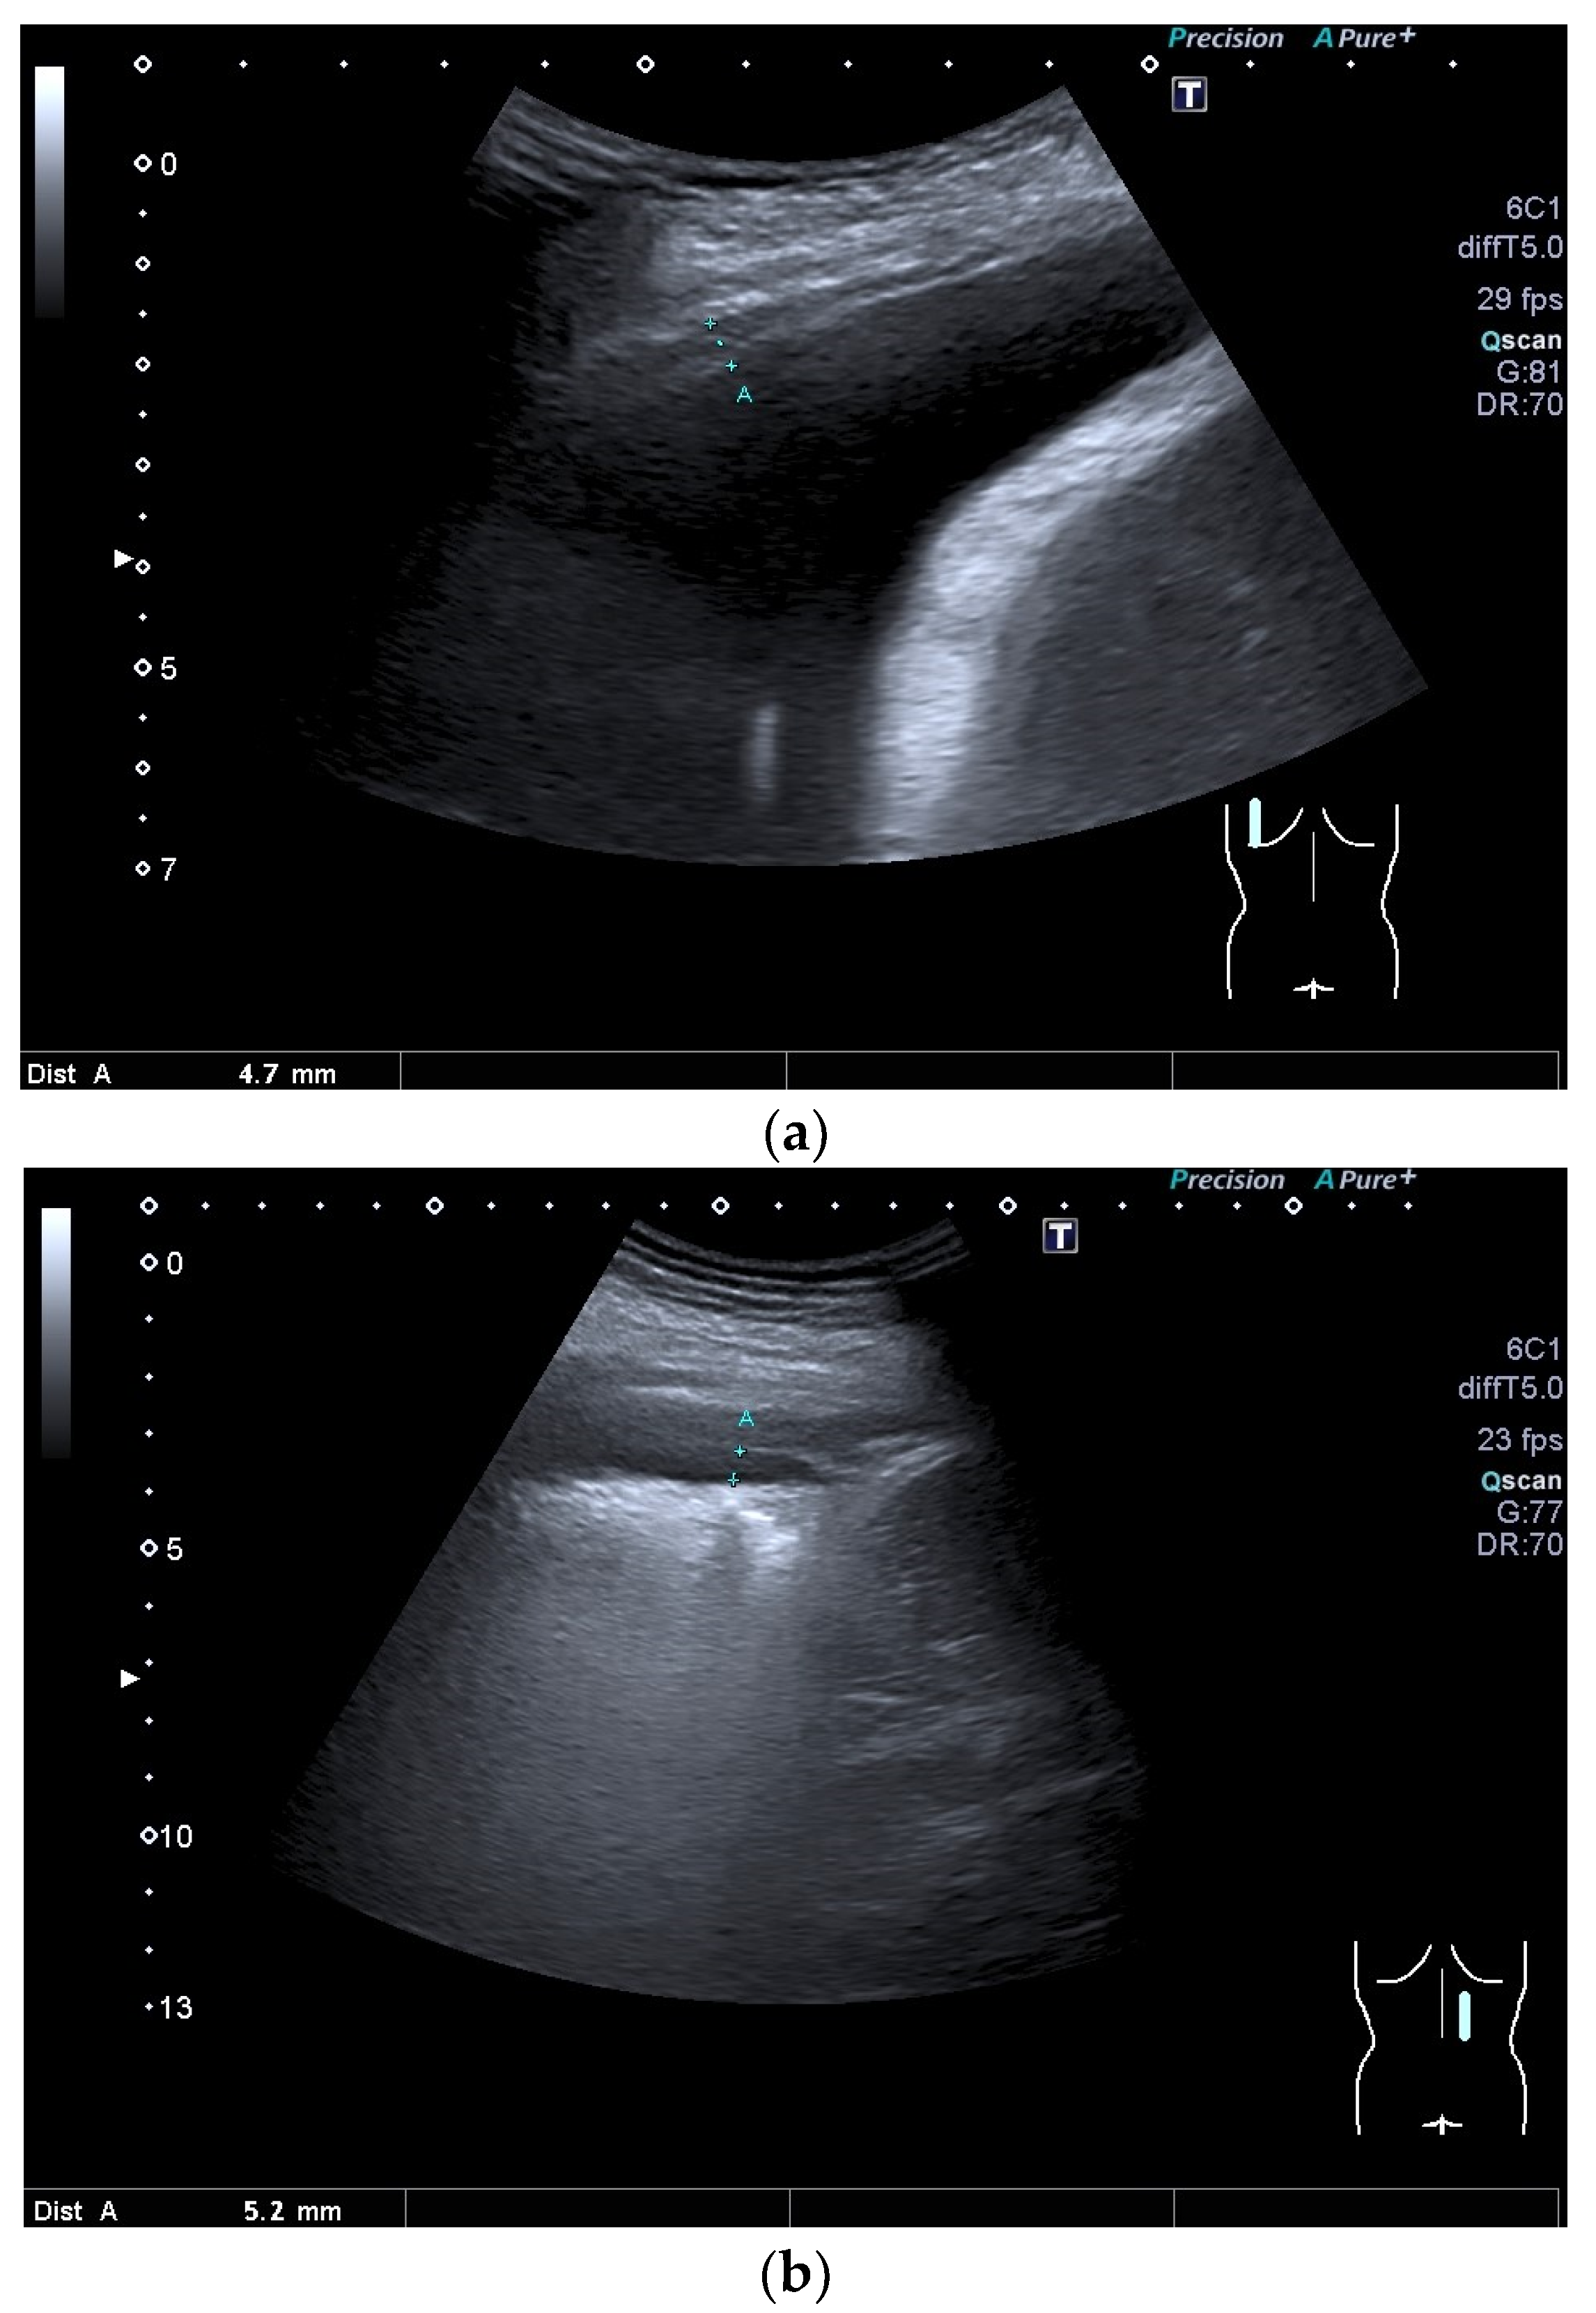

| Benign pleural thickening | Usually less than 10 mm thick, evenly thickened, no nodular thickening |